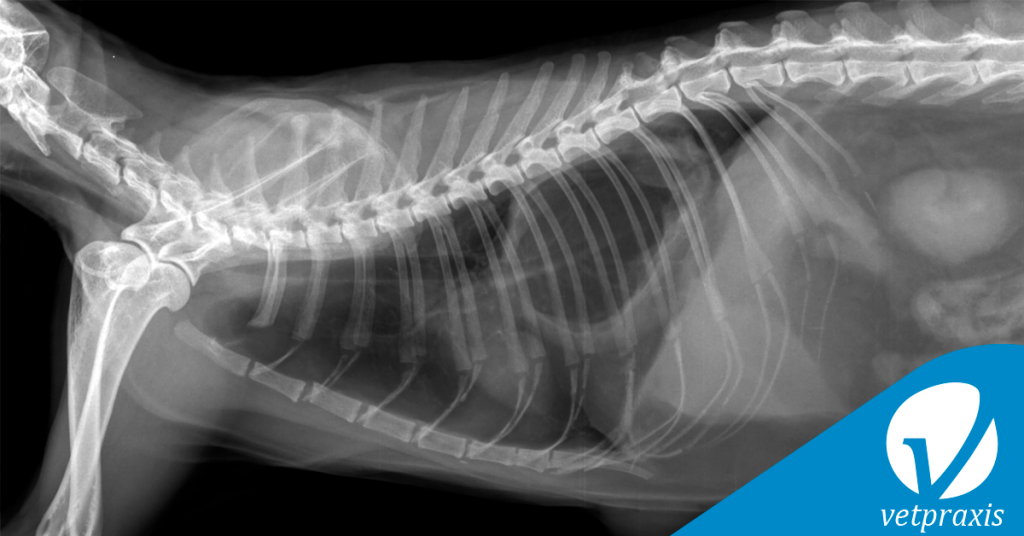

Paciente felino de 12 años con distress respiratorio severo peragudo, cianosis leve. Se presenta un abultamiento de pared corporal ventral a la altura de VIII esternebra.

Se adjuntan proyecciones simples L-L y V-D (de discreta oblicuidad) de tórax.

Indique el radiodiagnóstico considerando claves para justificarlo.

a) Rotura diafragmática traumática

b) Intususcepción gastroesofágica